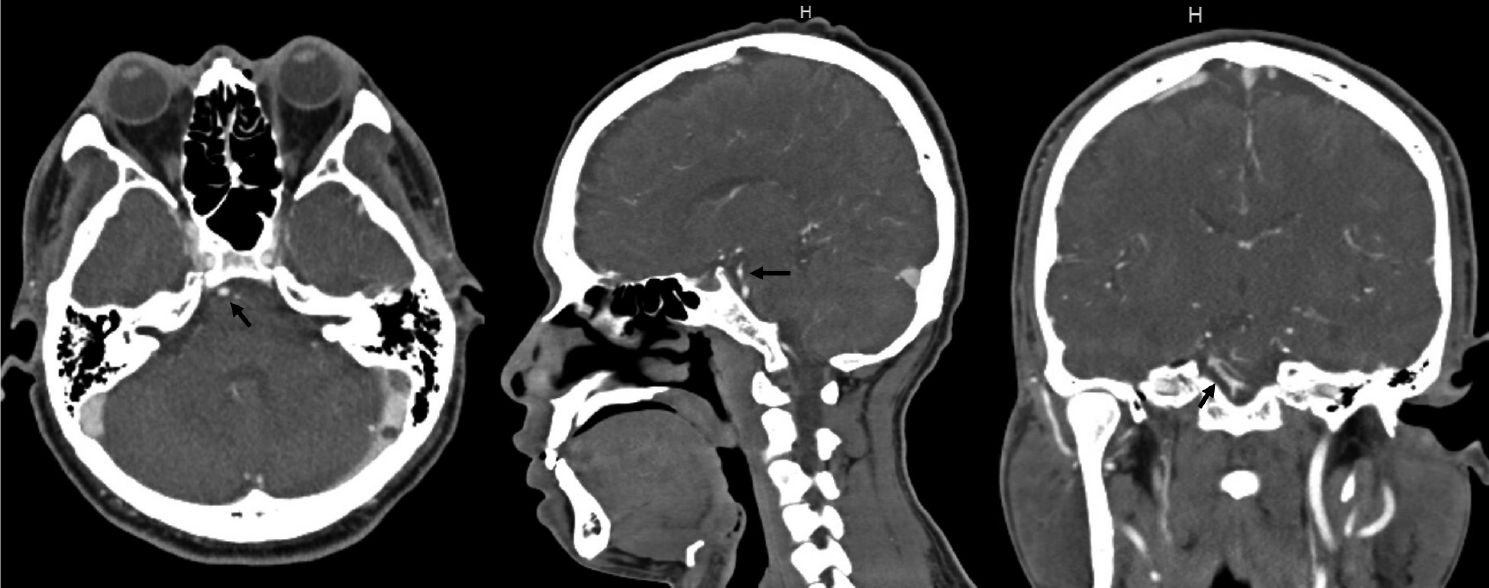

Blood pressure was 176/87 mmHg at the time of admission. Except for decreased hearing on the right side and an impaired right vestibulo-ocular reflex, the neurologic examination was unremarkable. Audiometry revealed a right moderate to severe sensorineural hearing loss. At the time, a head CT/CTA scan revealed no signs of vascular dilatations (Fig. 1).

Fig. 1.

Head CT/CTA scan done after emergency admission for vertigo and right hypoacusis. No signs of intracranial bleeding, vascular malformations, neoplasm or other relevant conditions. Specifically, no aneurysms or dissections can be seen arising from the basilar artery and right AICA (black arrow). CTA, computed tomography angiogram; AICA, anterior inferior cerebellar artery

Fig. 2.

Repeat head CT/CTA now showing a 9 mm fusiform aneurysm arising from the presumed AICA vessel (black arrow). CTA, computed tomography angiogram; AICA, anterior inferior cerebellar artery